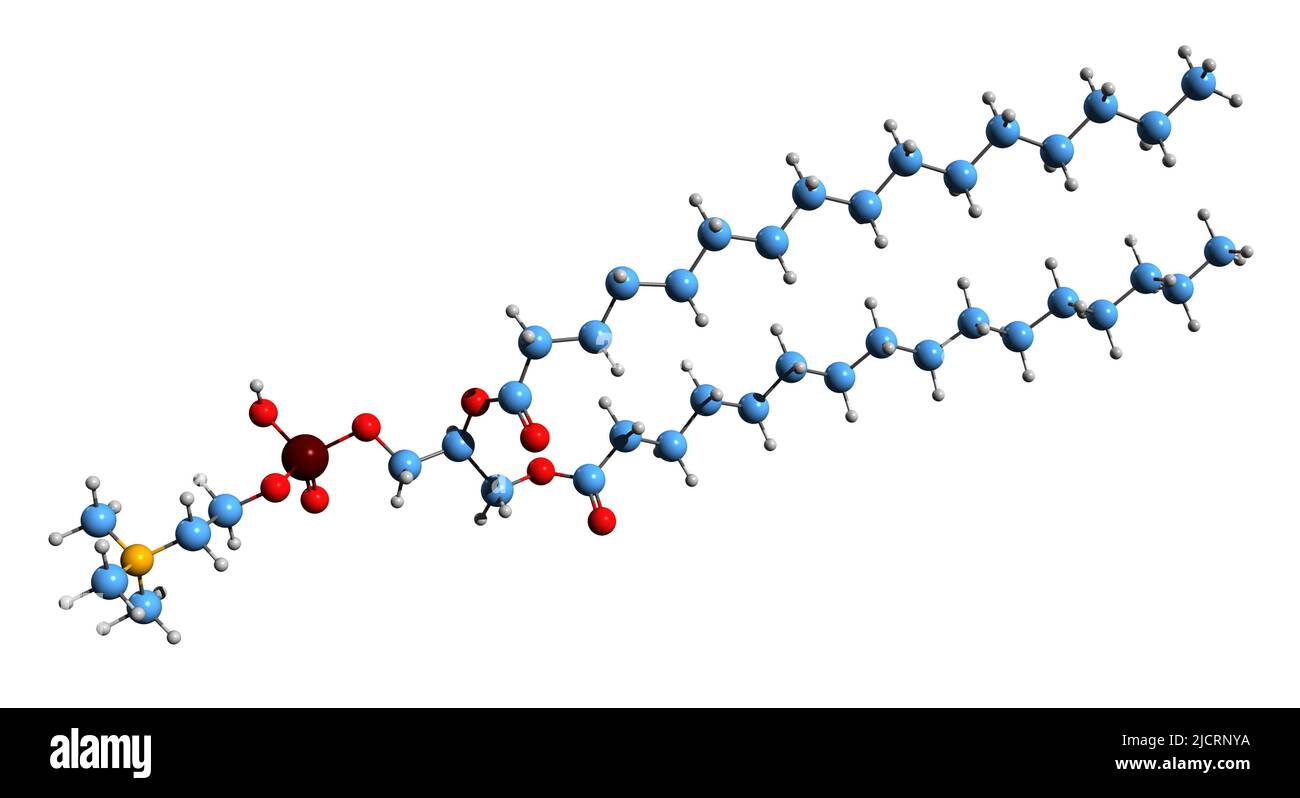

RF2JCRNYA–3D image de la formule squelettique du palmitate de Colfosceril - structure chimique moléculaire du surfactant pulmonaire isolé sur fond blanc